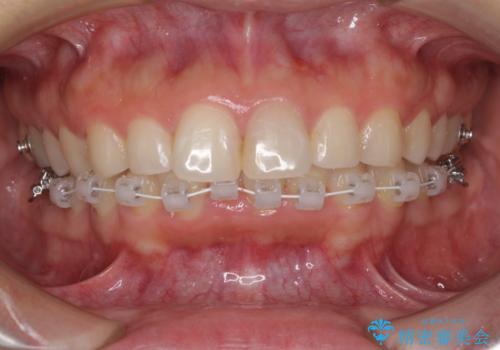

- 審美装置

- 治療期間

- 6ヶ月